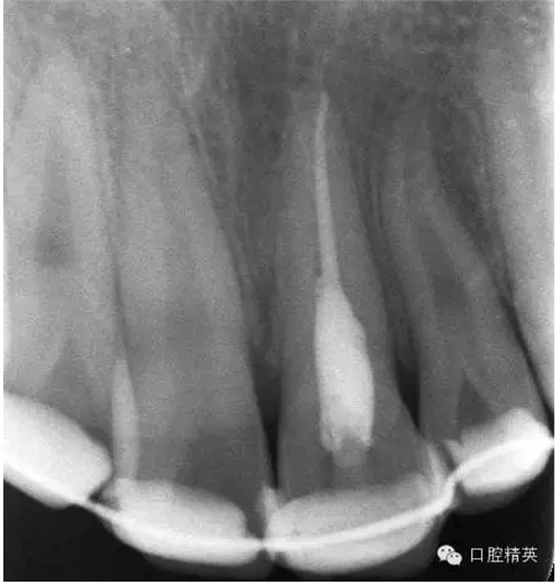

圖23.樹脂+牙弓夾板固定完成后的x線片影像

圖18.復(fù)位臨時固定后的x線根尖片?;颊哐栏c牙槽窩吻合。

圖19.經(jīng)過x線檢查,21復(fù)位和牙槽窩吻合,行13到23粘結(jié)部位的牙面全酸蝕。